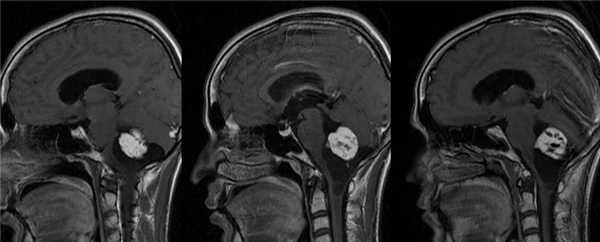

Образование на снимках МРТ.

Затруднения в диагностике гемангиобластомы связаны с неспецифичностью ее клинических проявлений, маскировкой неврологического дефицита и мозжечкового синдрома под выраженной общемозговой симптоматикой. Тщательный неврологический осмотр и дополнительная консультация офтальмолога, в ходе которой выявляются застойные диски зрительных нервов, позволяют заподозрить наличие внутричерепного объемного образования. При этом, кроме обычного первичного обследования в виде ЭЭГ, РЭГ и Эхо-ЭГ, пациенту в обязательном порядке должно быть проведено МРТ головного мозга.

В большинстве случаев исследование послойных горизонтальных и сагиттальных срезов, полученных при проведении МРТ, позволяет установить локализацию опухолевого процесса и дифференцировать его от абсцесса головного мозга, внутримозговой гематомы, очага демиелинизации при рассеянном склерозе, последствий тяжелой черепно-мозговой травмы, кисты головного мозга Окончательная диагностика гемангиобластомы и определение ее микроскопического типа возможны лишь после гистологического изучения образца опухоли. Необходимые для исследования опухолевые ткани могут быть получены в результате стереотаксической биопсии мозга или в ходе операции по удалению опухоли.

Компьютерная томография, магнитная резонансная томография выполняются с целью выявления опухолей центральной нервной системы и других системных изменений, связанных с синдромом Гиппеля-Линдау. Пациенты с двумя или более гемангиобластомами сетчатки являются носителями мутации гена VHL.